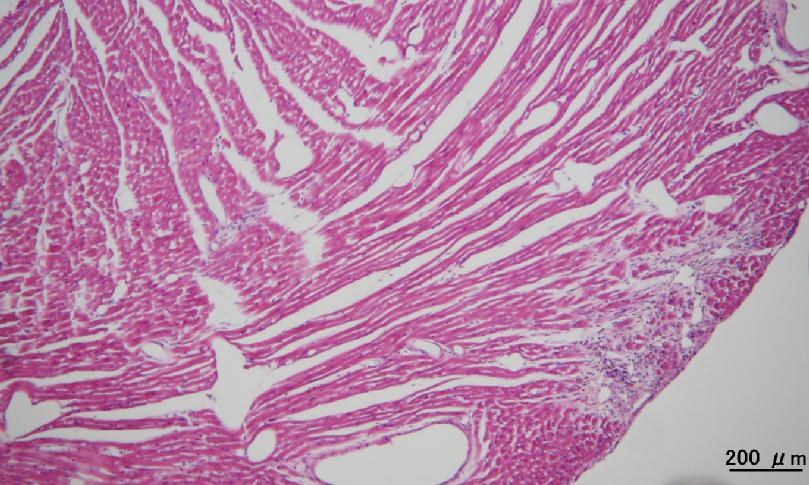

その後早稲田大学では、本開発装置を用いて、心筋梗塞モデルマウスのMCGを、生後間もない時期から経時的に計測する試みを行ってきた。そしてこれまでに、健常なマウスと不整脈を誘発したマウスのMCGが、それぞれ健常なヒトのMCGとヒトの不整脈発生時のMCGに類似していること、MCGによって疾患の発生が検出できる可能性があることを明らかにしてきた。そこで、心筋梗塞モデルマウスのMCG(磁場コンターマップ)に異常が計測された時点(図2参照。マウスAでは、10週齢時でS波時刻の磁場の吸い込みと湧き出しが9週齢時と比較して90度回転。マウスBでは、T波時刻において同様の変化を観測)において、該当するマウスの心エコー検査、血行動態検査、病理解剖検査を行い、心臓の異変状態や箇所を調べた。その結果、磁場コンターマップに異常が出現したマウスの解剖結果において、心筋梗塞の進行と思われるような症状が確認された。図3は心臓のスライス、図4はその拡大図である。マウスAでは冠動脈が太くなり、心室壁が肥大化していた(図3)。また図4より組織変成が進行しており、○印の部分に血液の浸潤が確認された。マウスBでは、同様に心室壁の肥大化が観測され、左心室において図4の○印の部分に組織の繊維化が観測された。

図4.心臓のスライス図拡大図